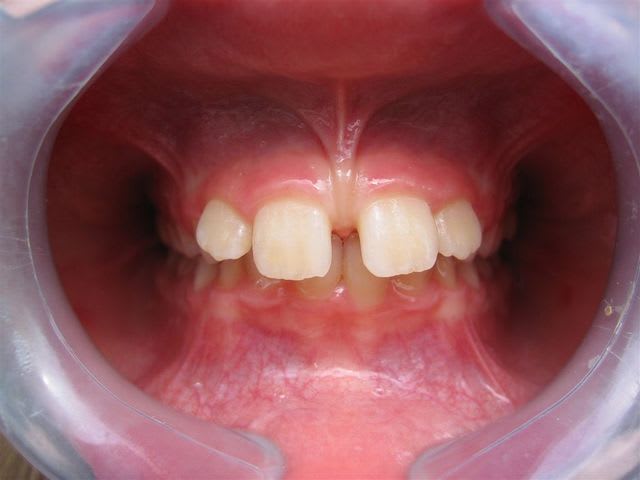

C’est un cas simple ou il faut juste stimuler un peu la croissance et reformer les arcades.

C’est le type même du traitement d’interception en denture mixte.

Pas de panique, petite DDM, bonne classe 2 sq,un peu de supracclusion ---> la laisser grandir un peu, et la confier à un ODF pour un peu de fonctionnelle et un alignement.

... elle est en classe I, avec une grosse supra.

TT "fonctionnel" prévu dans qqs semaines.

... c'est en cours ... un appareil de chez Rocky Mountain va être mis en place, à porter environ 16 heures/jour; il va falloir que je m'en fasse expliquer le principe lors de la séance de pose.

pour ta gamine je ne suis pas spécialiste mais il me semble que la première chose à faire est une freinectomie,suivie d'un apparei pour corriger l'occlusion

... freinectomie; elle se fait de moins en moins actuellement d'après l'ortho; et heureusement, je n'avais pas tellement envie de m'y coller!